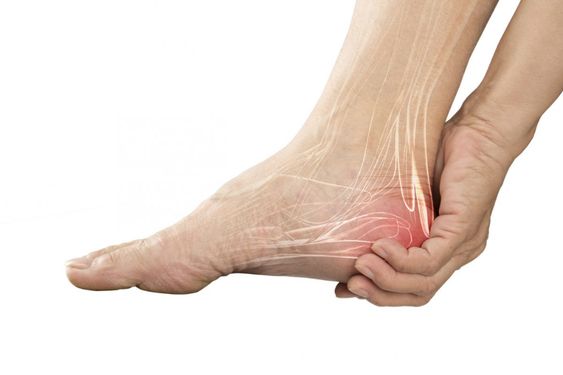

통증이 아주 심하면서 부기까지 일어날 수 있어요. 특히나 족저근막염이 급성 파열인 그럴 경우를 체크해 볼 수 있어요. 환부가 빨갛게 부어오를 수 있어요.

특히나 걸을 때 발뒤꿈치에 통증이 심하게 확인될 수 있어요. 주로 발뒤꿈치 안쪽에서 통증이 생기는 그럴 경우가 많은데요. 눌렀을 때 통증이 생기기도 해요.